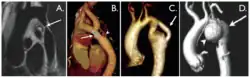

Coarctation of the aorta can be accurately diagnosed with magnetic resonance angiography. In teenagers and adults echocardiograms may not be conclusive.

The severity of coarctation of the aorta can be rated by a combination of the smallest aortic cross-sectional area of the aorta (adjusted for body surface area) as measured by 3D-rendered contrast MRI, as well as mean heart rate–corrected flow deceleration in the descending aorta as measured by phase contrast magnetic resonance imaging.[9]

Aortic coarctation using different imaging techniques[10]

Coarctation of the aorta